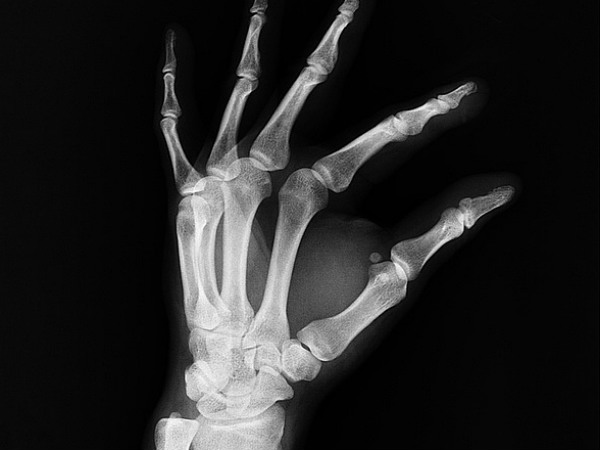

সম্প্রতি হওয়া বেশ কিছু স্টাডি অনুসারে গত কয়েক দশকে আমাদের দেশে যেহারে ভিটামিন ডি-এর ডেফিসিয়েন্সির মাত্রা লাফিয়ে লাফিয়ে বাড়ছে, তাতে এই সমস্যা প্রায় মহামারির আকার নিয়েছে। এমন পরিস্থিতিতে প্রয়োজনীয় সাবধানতা না নিলে কিন্তু বেজায় বিপদ। কারণ এই ভিটামিনটির সঙ্গে হাড়ের স্বাস্থ্যের সরাসরি যোগ রয়েছে। তাই ভিটামিন ডি-এর ঘাটতি হওয়া মানে ধীরে ধীরে হাড় দুর্বল হয়ে পরা। আর এমনটা হওয়া মানেই আর্থারাইটিসের মতো রোগ মাথা চাড়া দিয়ে ওঠা। প্রসঙ্গত, বার্হিমগাম ইউনিভার্সিটির গবেষকদের করা এক গবেষণায় দেখা গেছে মানব শরীরে ভিটামিন ডি-এর ঘাটতি দেখা দিলে রিউমাটয়েড আর্থ্রাইটিসে আক্রান্ত হওয়ার আশঙ্কাও মারাত্মক বেড়ে যায়। তাই জীবনকে যদি কষ্টের জেল খানায় বন্দি করে ফেলতে না চান, তাহলে এই ভিটামিনটির ঘাটতি হতে দেবেন না। প্রসঙ্গত, এক্ষেত্রে আরেকটি বিষয়ও মাথায় রাখা জরুরি যে ভিটামিন ডি হাড়কে শক্তোপোক্ত করার পশাপাশি হার্ট, ব্রেন এবং শরীরের রোগ প্রতিরোধ ব্যবস্থা শক্তিশালী করে তুলতেও বিশেষ ভূমিকা পালন করে থাকে।